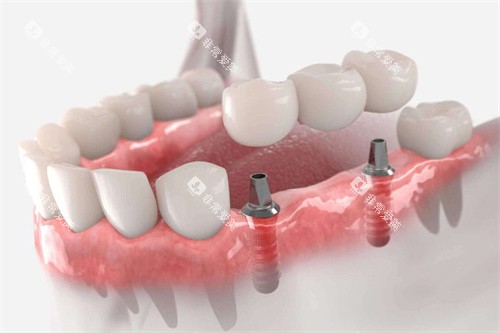

种植牙是通过外科手术将人工牙根植入牙槽骨内,然后在上面安装牙冠的修复方式,被誉为""人类的第三副牙齿""。

种植牙更大优点是不损伤邻牙,能够有效防止牙槽骨萎缩,咀嚼功能接近真牙,使用舒适度高。根据临床数据,种植牙可行性高达90%以上,使用年限通常可达10-20年,是长效性修复方案。

主要缺点是价格昂贵,修复周期长(通常需3-6个月),且需要手术,对患者的牙槽骨条件和全身健康状况要求较高。部分患者可能需要植骨,增加额外费用(骨粉、骨膜约2000-3000元)。

种植牙适合全身健康状况良好、牙槽骨条件充足(或可通过植骨改善)、对修复结果要求高且经济预算充足的患者。尤其适合不愿磨损邻牙的年轻患者。